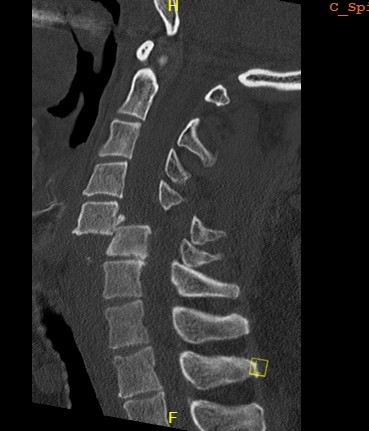

Unilateral facet joint dislocation on CT

Bilateral jumped facets on CT